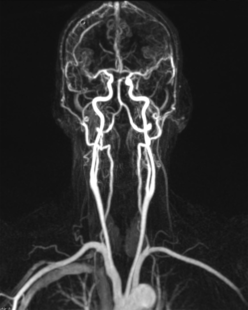

Magnetresonanztomografie:

Die Gefäßdarstellung erfolgt in einem modernen 48-Kanal-Magnetresonanztomografen (Siemens Area 48) der mit spezieller Hard- und Software für die Darstellung aller Gefäße des Körpers ausgerüstet ist. Dazu wird überwiegend ein gadoliniumhaltiges Kontrastmittel verwendet, welches meist über eine Armvene injiziert wird. Die Untersuchung dauert ca. 10 – 20 Minuten.

Neben der Erfassung von Veränderungen des Gefäßdurchmessers zur Beurteilung der Durchblutungsstörung, liefert uns diese Untersuchungsform auch wichtige Information zum Aufbau der Gefäßwände, zum Beispiel bei entzündlichen Gefäßerkrankungen und zum Nachweis von durchblutungsgestörtem Gewebe.